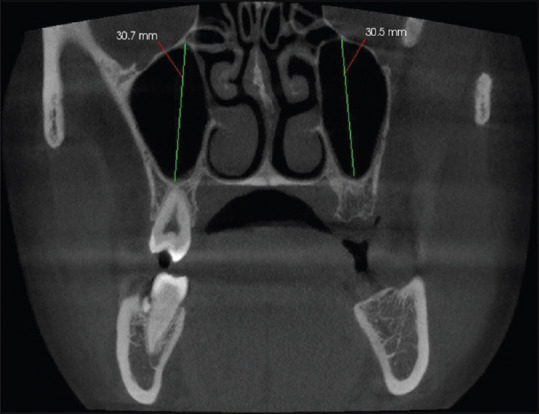

Materials and methods: The reporting of the study was done in accordance to strengthening the reporting of observational studies in epidemiology guidelines/checklist. Two hundred CBCT scans (400 MSs) were analysed for height and width of the maxillary sinuses (MSs) and its distribution with regards to gender. The prevalence of AMO and its different types of shapes were evaluated.

Results: Between the male and female groups, differences on both the right and left sides with respect to the MS height were observed (P > 0.05). However, the male group showed statistically significant higher values for right-sided MS width (P < 0.05). The prevalence of AMO in 400 MSs was found to be 65%, of which 63% of AMOs were present in the male group. The prevalence of types of accessory maxillary ostia revealed that the round and ovoid shapes were similar in number as compared to slit shapes.